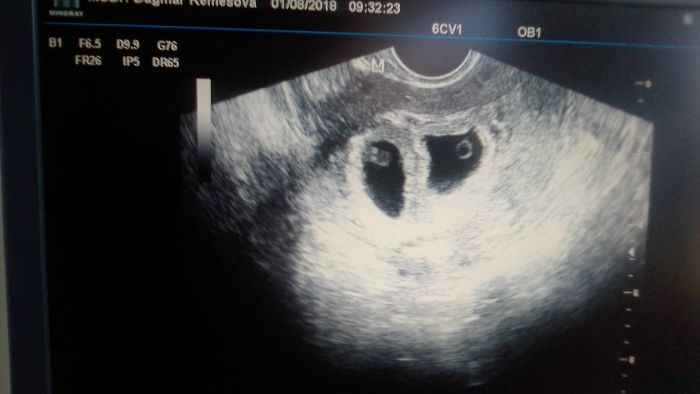

AAhoj tak sem byla u doktora a sem tedy 7tt a čekám dvojčata ale nemám stoho radost mám už 3 letou holčičku a chtěla jsem jen jedno tak teď nevím co dělat přítel si nepřeje abych šla na interupci ale jsou to velké starosti tak newim co dál